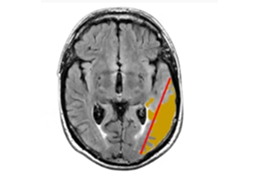

成像智能。

Eclipse 成像智能功能提供强大的处理能力和最佳质量的影像,同时减少质量错误并提高剂量效率。

凭借 AI、专有算法和先进的影像处理能力,提供出色的影像质量和无与伦比的诊断信心。